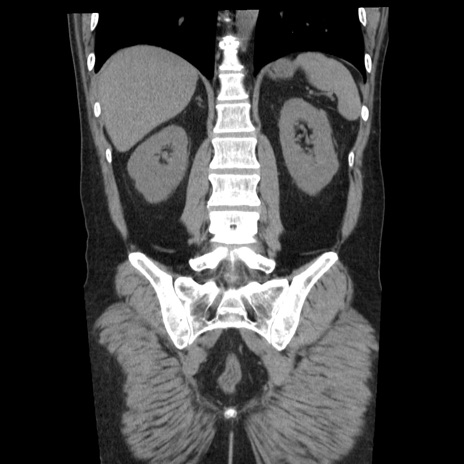

症例29(冠状断像)

【症例】40歳代男性

【現病歴】2日前から胃痛あり。徐々に周期的な激痛に変化した。本日になっても激痛があるため受診。

【身体所見】意識清明、BT 38-39℃台あり、腹部:膨満、やや硬、右下腹部に圧痛あり。

【データ】WBC 8500、CRP 23.26